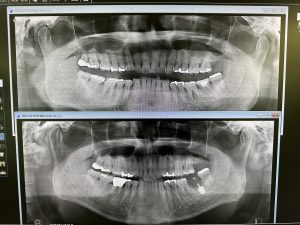

土曜日、本日は2件オペ

御二方共に一本のみ、抜歯即時に成熟埋入

結果20分から30分で終わり、ストレスなし

計測値も良く6w後には仮歯印象だね